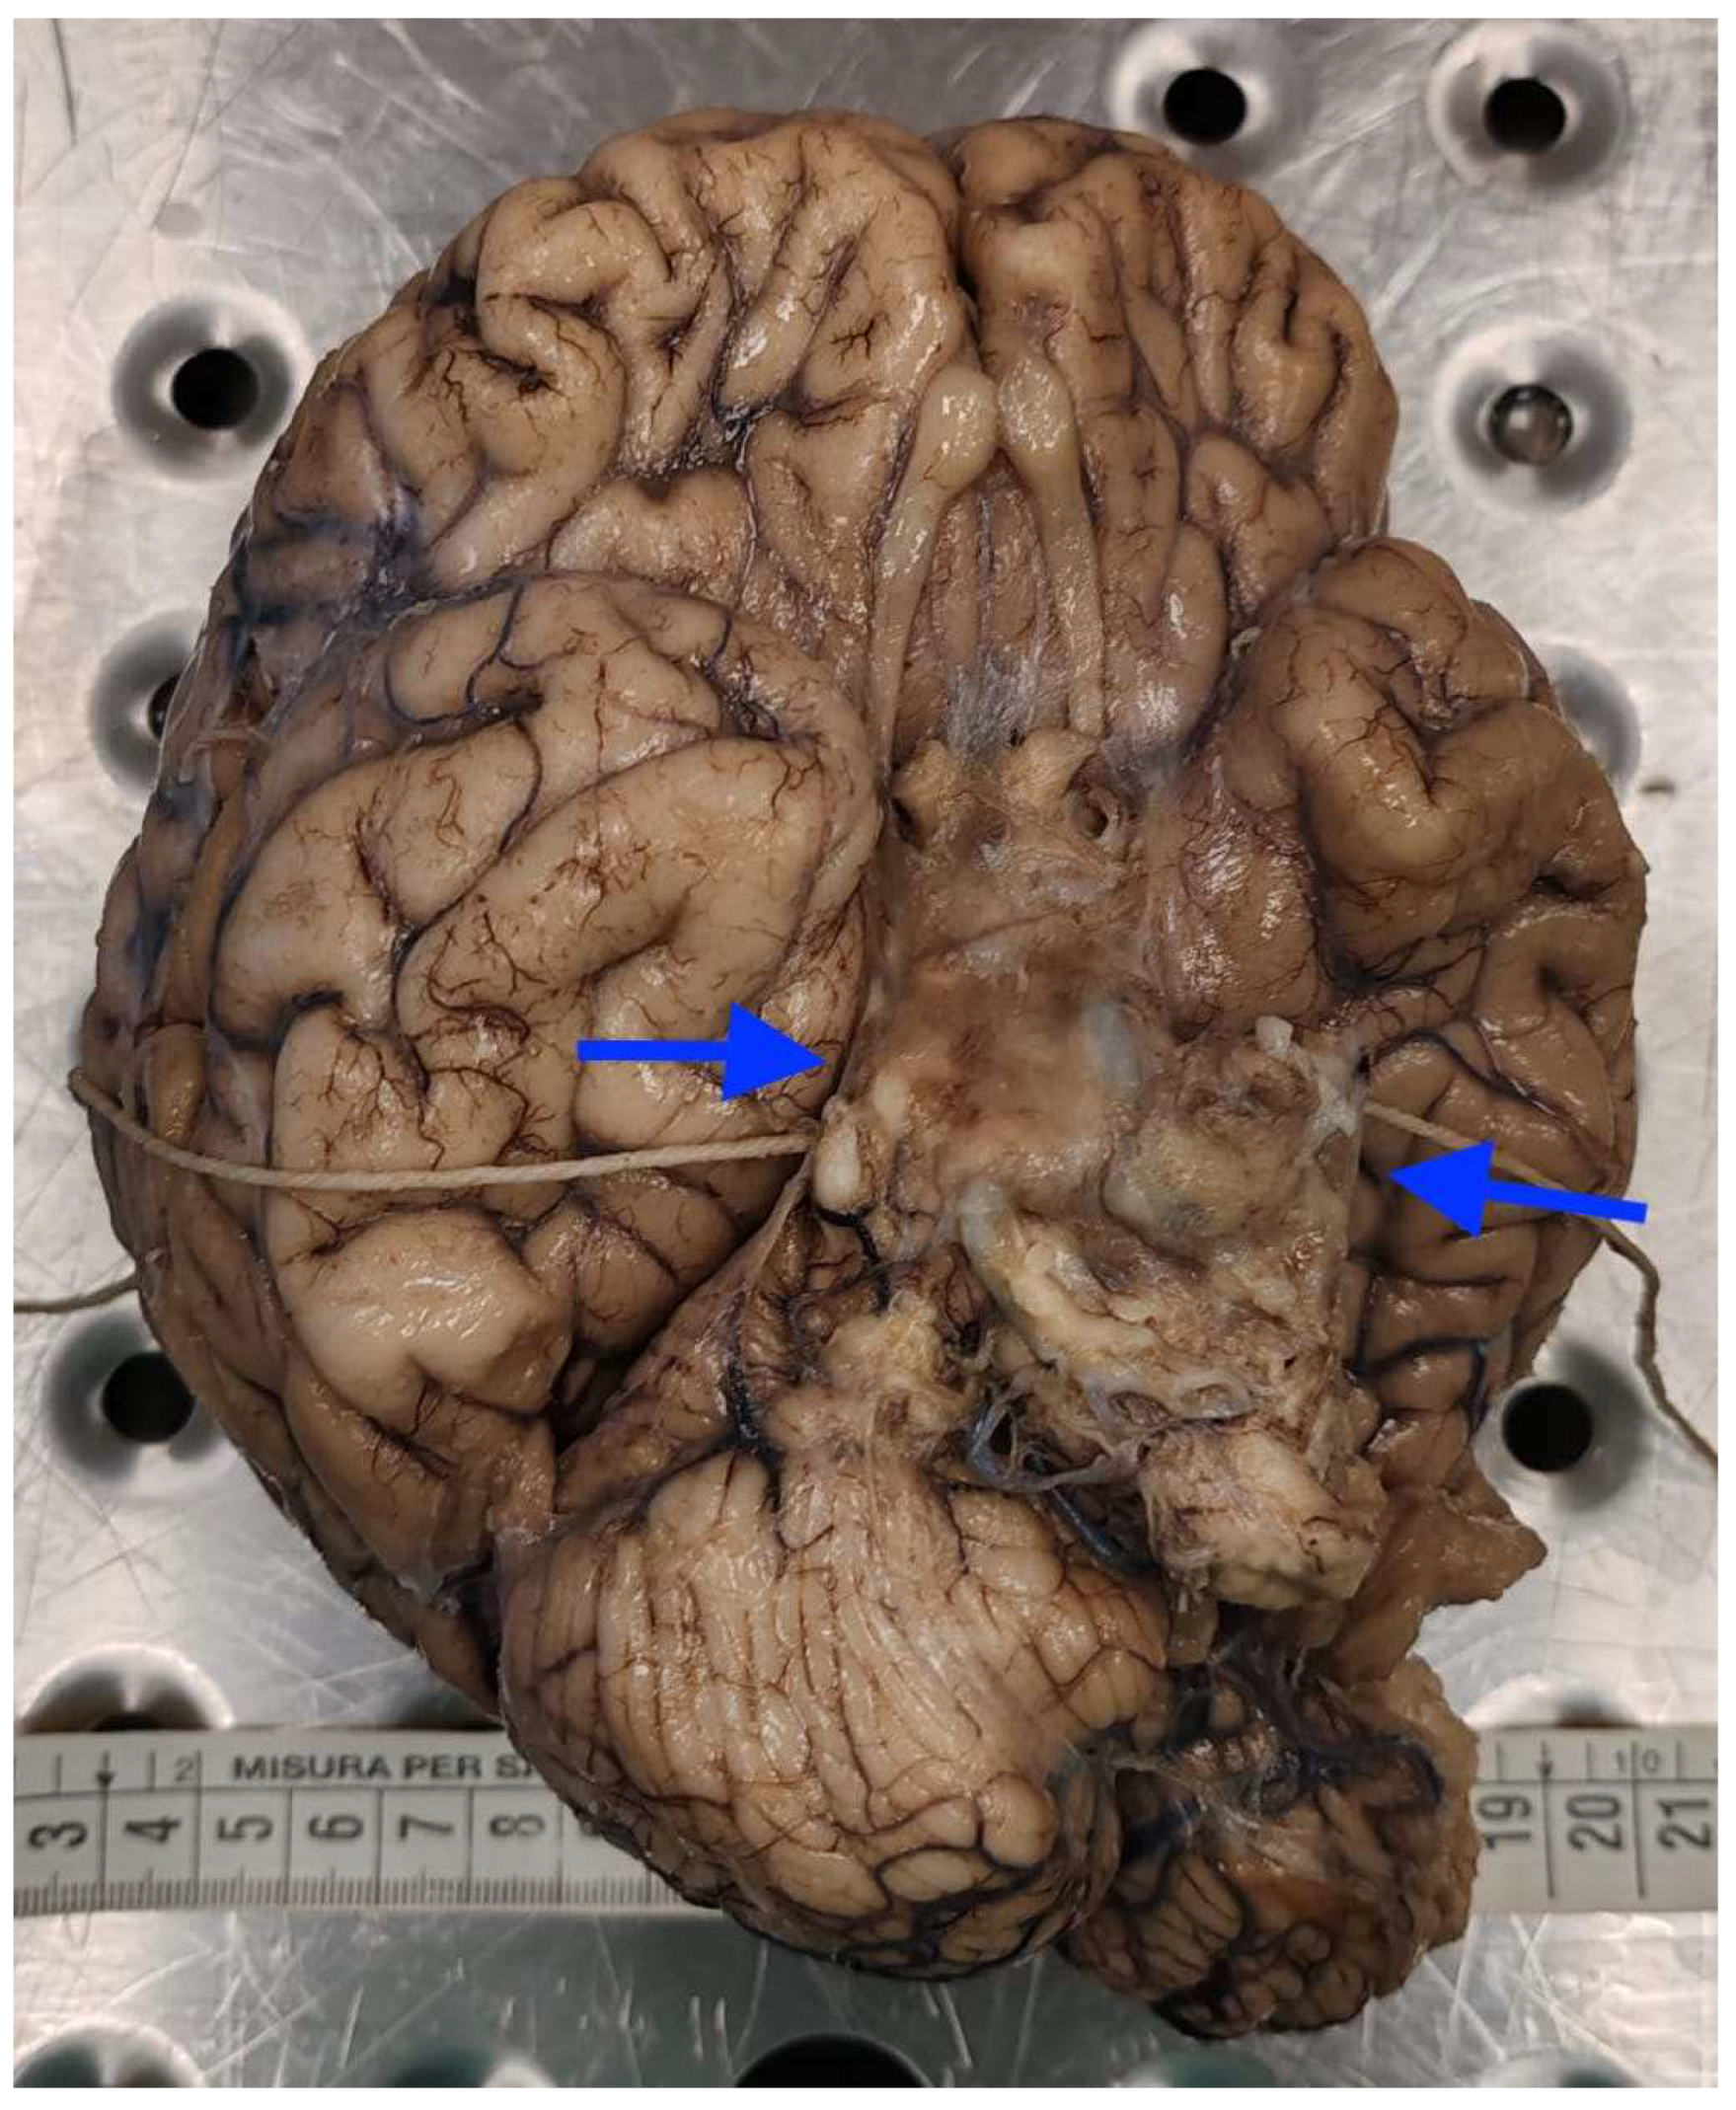

| ~3 months after surgery | Progressive neurological decline, coma, death | Autopsy: PAS-D and GMS stains positive for fungal elements (Candida albicans) | – | Supportive intensive care until death |